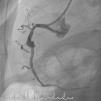

Homem, de 63 anos, recorre ao serviço de urgência do hospital mais próximo do local de férias por indisposição generalizada e dor mandibular com quatro horas de evolução, sendo diagnosticado enfarte agudo do miocárdio (EAM) da parede inferior. Já tinha antecedentes de EAM há quatro anos, em França, tendo colocado stents na coronária direita e circunflexa. Dado ser um centro sem capacidade de angioplastia, realizou fibrinólise nos primeiros 30 minutos, sendo depois transferido para centro com a mesma valência. A coronariografia revelou volumoso aneurisma no segmento médio da coronária direita em relação com porção proximal de stent, com trombo recanalizado (Figura 1). Foi tentada angioplastia para exclusão de aneurisma, mas não foi possível atravessar o stent com os fios guia utilizados. Ficou a ideia que a porção proximal do stent estaria ocluída, fazendo‐se o fluxo através da malha lateral. Dias depois fez‐se nova tentativa de angioplastia, apresentando aspeto de trombo organizado (Figura 2). Cruzou‐se a malha lateral do stent, mas não foi possível progredir um balão (Figura 3). A Figura 4 evidencia o resultado final.